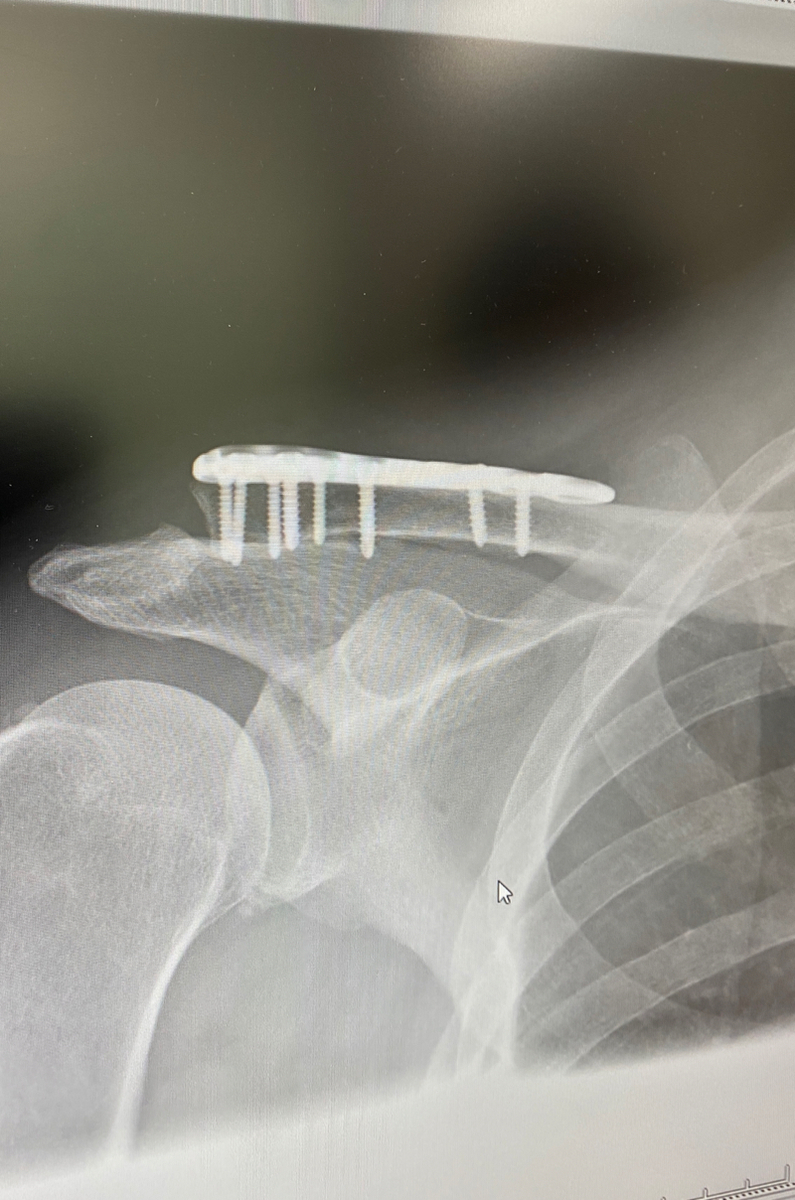

3 金属のプレートを外した場合のメリットとデメリット 31 プレートを外した場合のメリット 311 ①熱や冷えのストレスから解放される 312 ②違和感から解放される 313 ③交通事故のことを思 鎖骨骨折を手術療法で過ごした1年間 1年前の1月18日に鎖骨を骨折した。 チタンプレートとボルトで折れた骨を固定する手術療法を選択。 骨折は治癒に年単位かかると言われ、プ 金属のプレートとボルトを抜く手術の入院期間 私が抜釘手術で入院した期間は2泊3日でした。 私は2泊3日の入院期間でしたが、どうしても忙しいという人は 1泊2日でも可能 だ

鎖骨 骨折 プレート 手術 費用- まだプレートは入ったままですが、また半年後に摘出しましょうとの事。 一応完治しました。 11月21日に手術をして翌年2月1日で完治だとの説明を受けましたので、 全治10週間 くら には、プレートやワイヤーを使用して骨折部位を結合させる手術を行います 。 手術前、手術後にかかわらず鎖骨骨折の痛みが強い場合は、鎮痛 薬の処方を受けることもできますので

鎖骨骨折の治療 鎖骨骨折の治療法は保存療法と手術療法に分けられます。 保存療法 鎖骨骨折は比較的予後が良好であるため、多くは保存療法が選択されます。 骨の転移が大きくな

骨折観血的整復固定 鎖骨骨折 浜脇整形外科

鎖骨骨折手術の様子について 社会医療法人 有隣会 東大阪病院 看護部 大阪の看護師求人 看護師転職